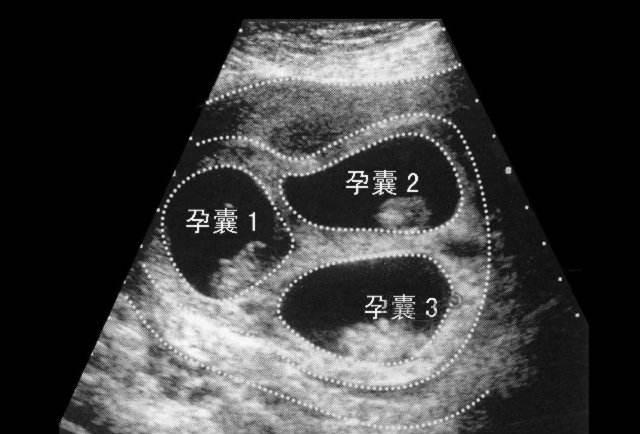

怀双胞胎或多胞胎对母亲和婴儿都有相当大的风险,如并发症、孕妇羊水过多、感染、卵巢过度刺激综合征、早产、出生体重低,甚至婴儿智力低下。所以对于一些特殊情况的双胎孕妇,有必要进行减胎手术。

双胎减胎最好在怀孕8-11周,最晚不超过28周。有时缩胎时间,也需要根据孕妇和胎儿的具体情况进行分析,所以不同情况下的减胎时间是有一定差异的。孕妈妈要去医院诊断,听从医生的建议,选择好的减胎时间,这样可以保证另一个胎儿的正常发育,也不会对孕期身体造成伤害。